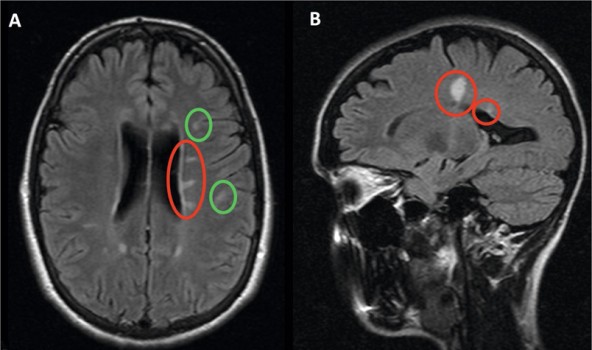

De diagnose MS staat of valt met het aantonen van demyelinisatie op meerdere plaatsen in het centrale zenuwstelsel (waartoe ook de oogzenuw behoort), die recidiveert en waarvoor geen andere verklaring is te vinden.4 In de afgelopen decennia is MRI een steeds grotere rol gaan spelen in de diagnose, die meestal kan worden gesteld op basis van het klinische beeld en de MRI-bevindingen [figuur 1]. Hierdoor is een lumbaalpunctie meestal niet meer nodig.

Figuur 1 | Voor MS kenmerkende MRI-afwijkingen

De grootste voorspeller voor het beloop is de eerste MRI-scan: hoe meer afwijkingen op die scan, hoe groter de kans op een slecht beloop. Ook afwijkingen in de hersenstam of het ruggenmerg zijn prognostisch ongunstig. Iemand die zich presenteert met een oogzenuwonsteking en op een MRI van de hersenen reeds 20 afwijkingen heeft (die dus ergens in het verleden zijn ontstaan), heeft een duidelijk grotere kans op meer letsels in de toekomst dan iemand bij wie slechts 2 afwijkingen te zien zijn. Sommige patiënten hebben vooral letsels in de hersenstam en/of het ruggenmerg, structuren die zo cruciaal zijn dat alles wat daar gebeurt bijna direct klinische consequenties heeft, maar de hersenen kennen ook veel ‘stille’ gebieden waar een laesie minder gevolgen heeft. In de dagelijkse praktijk is het dus goed mogelijk om een prognostische inschatting te maken en het behandelplan daarop te baseren.